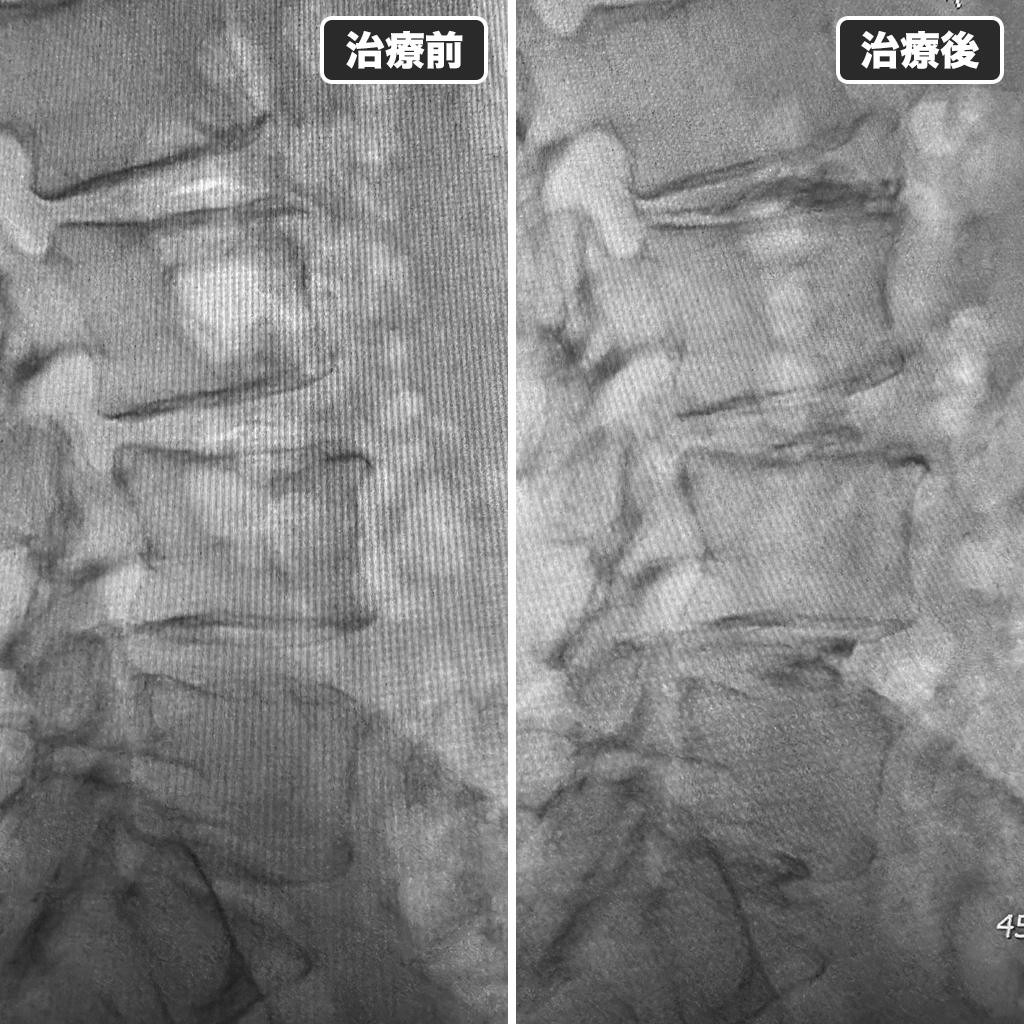

Annulargram検査

椎間板治療前にAnnulargram検査を行っています。北米ではこの検査を行わないまま治療を行うと裁判になって負けてしまうと聞いています。

ディスクシール治療

検査により損傷部分を確定させてディスクシール治療を行っているところになります。

治療前後のレントゲン写真

左側が治療前で右側が治療後になります。ゴルフの再開は1ヵ月後とご説明しております。治療中は鎮静剤を使用しましたので、不安や痛みもなく大変満足していただけました。